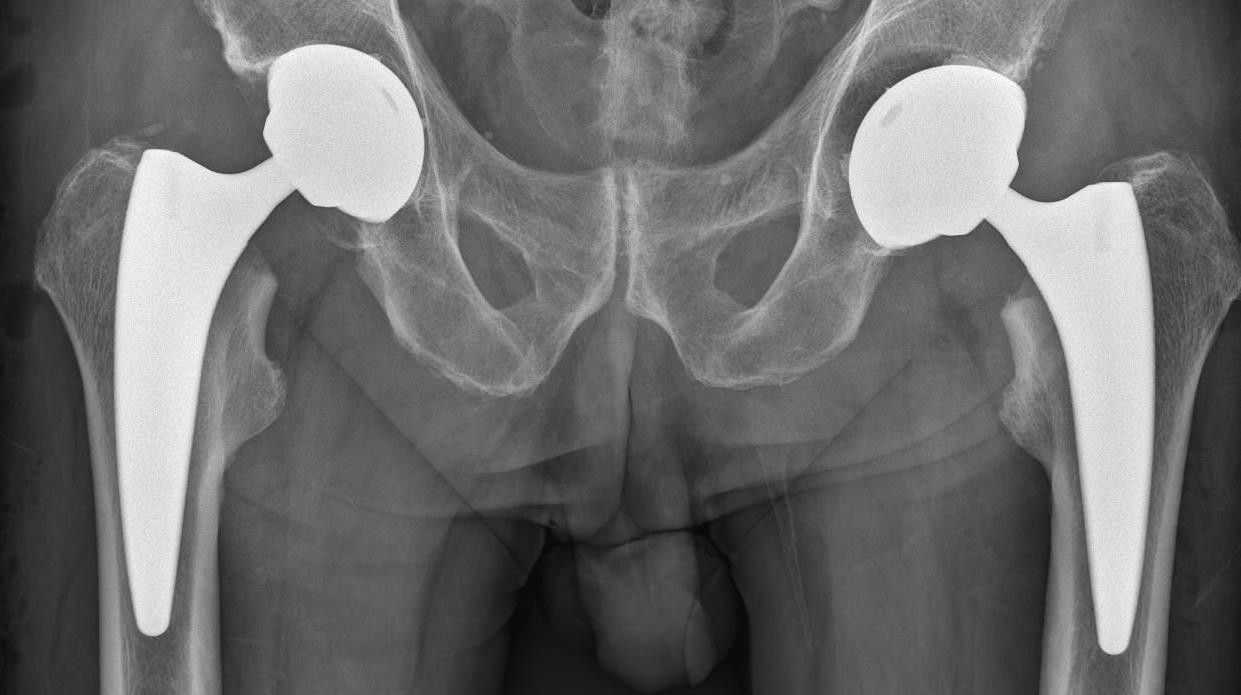

Mit 70 Jahren geht Manfred Weissinger als ärztlicher Leiter der Waldviertler Kliniken Zwettl, Gmünd und Waidhofen in Pension. Bekannt wurde er unter anderem durch seine im Jahr 2003 entwickelte "Zwettler Hüfte".

Sie stellte einen Durchbruch in der Orthopädie dar und kann nur durch einen verhältnismäßig kleinen Hautschnitt – im Vergleich zu vorhergehenden Methoden – eingesetzt werden. Am MIttwoch wurde Weissinger nach fast 40 Jahren offiziell verabschiedet.

Durch die "Zwettler Hüfte" wurde er bekannt.

Neben der "Zwettler Hüfte" setzte Weissinger auch im Knie- und Schulter-Bereich starke Akzente, ebenso gilt er beim Einsetzen einer künstlichen Bandscheibe in der Halswirbelsäule unter dem Mikroskop als Top-Mediziner. Damit wurde 2017 der Rekord von 1.170 eingesetzten Prothesen in Zwettl erreicht. 1.000 waren es im Vorjahr.